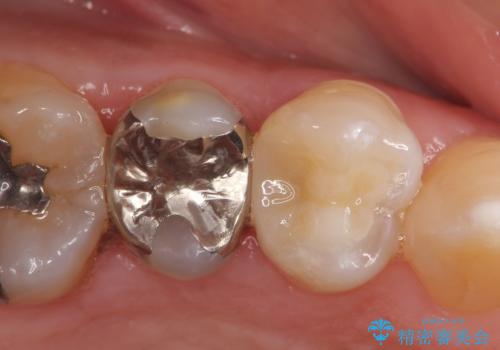

保険治療は見えない部分で状態が悪化している

- 金属を除去し、下に広がる虫歯や古い材料の処理をおこなう

→虫食い状になった歯を新しい材料で整理し、セラミックインレーを完成させる。

保険治療は、「銀色」ということが悪いのではなく、「処置がいい加減」なのが悪いのです。

自費治療は、「白い」のが良いのではなく、「丁寧で妥協のない処置」なのが良いのです。